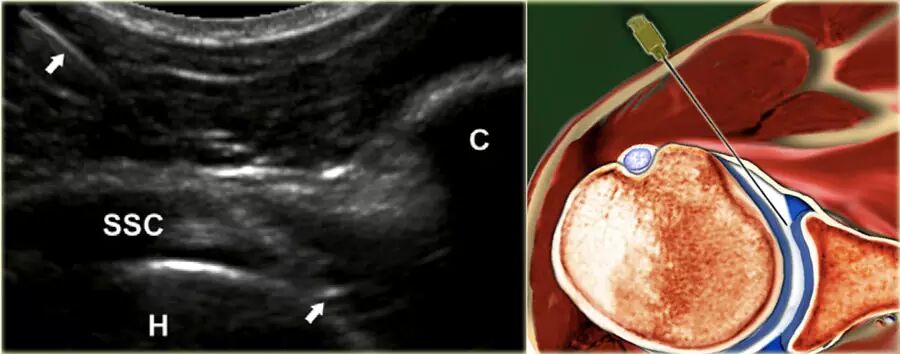

前路途径   在前路方法中,患者仰卧仰卧,伸出的手臂外旋(图)。超声探头在腹侧平行于肩胛腱的长轴放置。探头侧的灰线表示长轴。

如果使用直径为21号或更细小的针头,则不需要局部麻醉。由于抽吸物的高粘度,可能需要使用较大的钻孔针, 在这种情况下,指示局部麻醉。为了便于注射药物或对比剂,可以在针和注射器之间使用连接管,注射器由助手保持和管理。

使用22号针,针连接到包含造影剂的50mL注射器,由助手保持,在适当的针位置注射15-20mL造影剂时,针垂直于肱骨头的内侧边缘前进,穿透肩胛腱。

如果刺中肱骨头的软骨,针应该拉回1或2毫米,稍微倾斜大约15◦,然后前进切向与头部进入关节,针的斜面朝向关节(图) 。不应该感觉到注射阻力,并且应该看到对比剂自由进入关节并且存在于肩胛下凹部中。